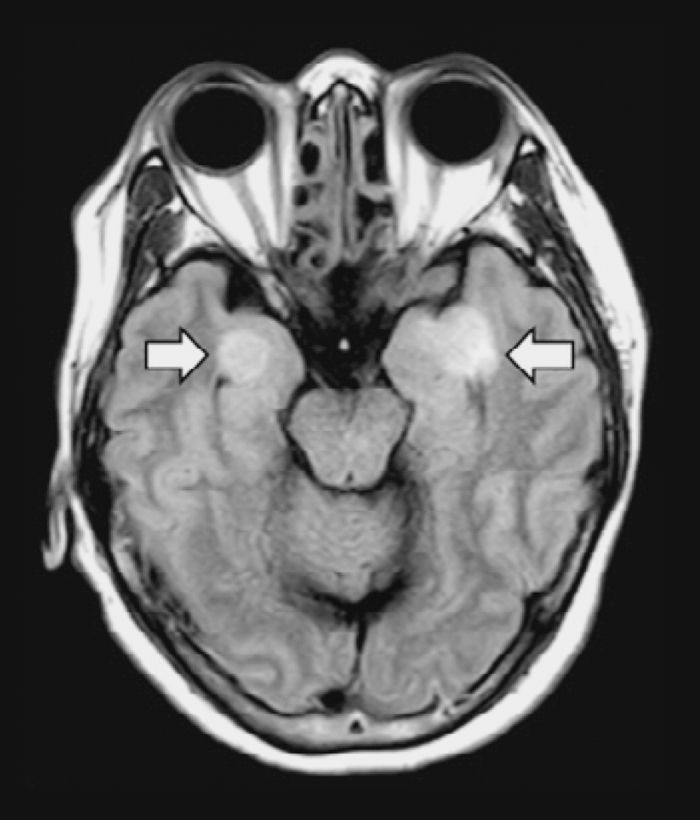

4月3日 , 日本研究小组在《国际传染病杂志》上发表了一项案例研究 , 研究表示在一名患有脑膜炎和脑炎的COVID-19患者的脑脊液中发现了新冠病毒 , 表明新冠病毒也可以攻击大脑和神经系统 。

本文图片

箭头指向为大脑组织受损部位